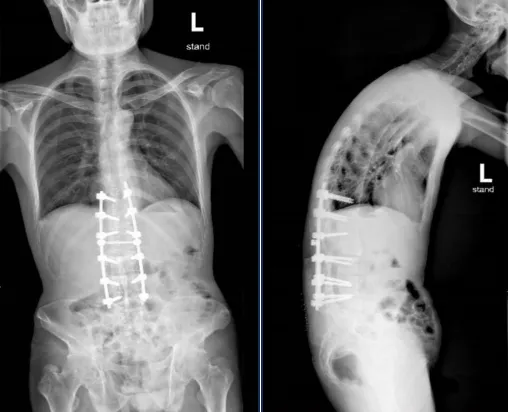

▲患者手术后脊柱正、侧位片